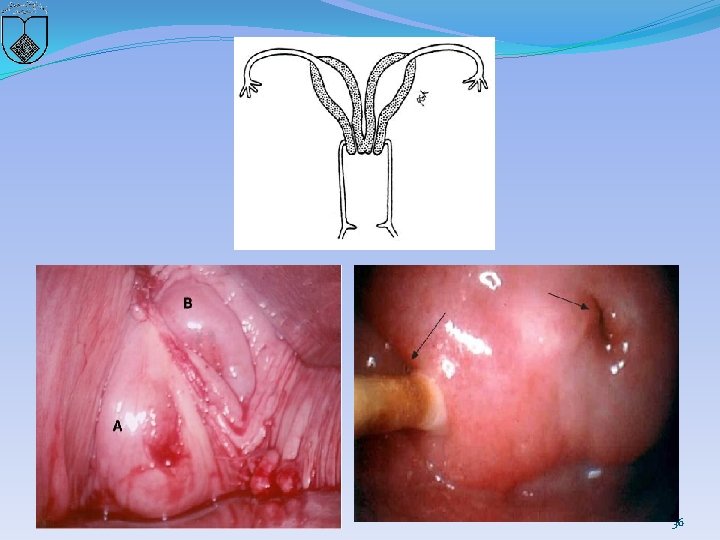

Congenital cervical anomalies �If one or both müllerian ducts fail to fuse, or if development of one or both ducts does not occur, or is incomplete, duplication or agenesis of the cervix can occur. � Coexistent anomalies of the vagina, uterus, and urinary tract are common since anomalies of the mesometanephric duct frequently occur in association with those of the müllerian ducts 27

Duplication of the cervix �Two distinct cervices or two fused cervices �It may be difficult to differentiate and determine if there are two separate cervices or if there is a single cervix with a septum. �Nonobstructive duplication of the cervix is usually asymptomatic and does not require intervention. �Obstructive lesions require surgical intervention (described below) if hematometra or pyometra occurs. � In cases of cervical duplication with a longitudinal vaginal septum or an obstructed hemivagina, great care should be taken when removing the septum so as not to compromise the blood supply to the individual cervices 28

36